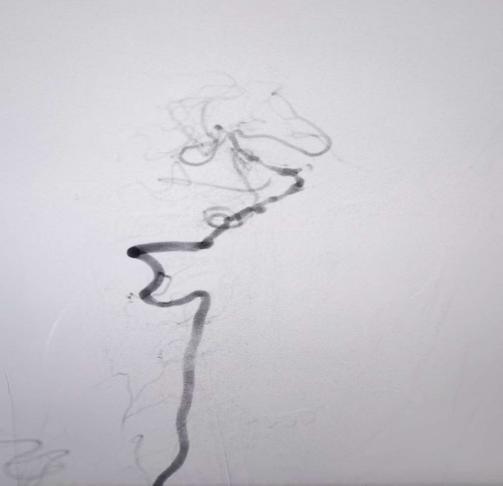

值班医生立即向神经内四科主任包瑛汇报病情,经评估,患者符合血管内介入治疗指征,需立即行基底动脉取栓术。在与患者家属充分沟通病情后,医院迅速启动导管室绿色通道。由包瑛带领的介入团队开展手术,术中造影证实患者基底动脉中段闭塞,且手术路径困难,患者还合并有多发动脉瘤,随时可能破裂。在介入团队的精湛操作和不懈努力下,成功为患者实施了基底动脉支架取栓及球囊扩张成形术,闭塞血管被成功开通,实现了血流再通。术后,患者被转入卒中单元进行严密监护,病情逐步稳定,为后续康复奠定基础。